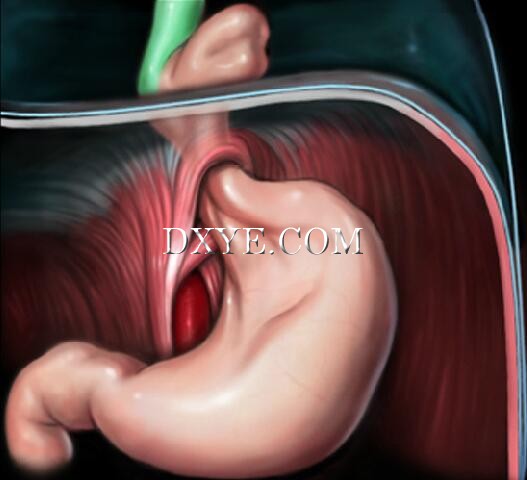

• Stage 1

Sliding hiatal hernias occur when the abdominal esophagus migrates through the hiatus while the gastroesophageal junction (GEJ) and stomach remain below.

As the abdominal esophagus migrates, the EGV disappears due to the widening of the esophagogastric angle, and the LESE diminishes due to the loss of anatomical relationships and extrinsic pressures.

This may not be appreciated on endoscopy or barium study.

This would explain the reports of GERD without a hiatal hernia.